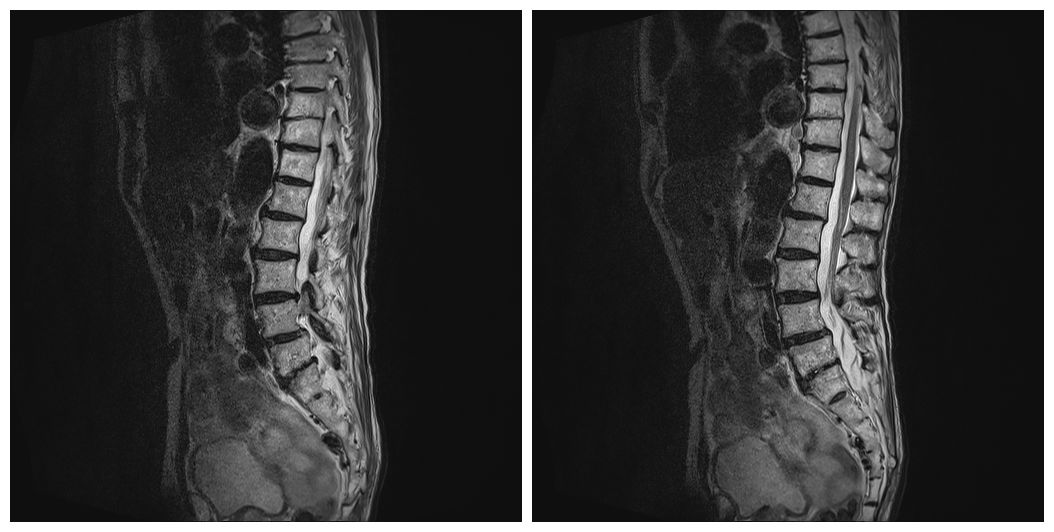

3月21日,复查腰椎MRI提示L5、S1椎体及周围软组织异常信号,考虑感染可能大,较前进展。T12椎体异常信号,血管瘤。腰椎退行性变并L4椎体不稳(图1)。

图1 患者腰椎MRI结果